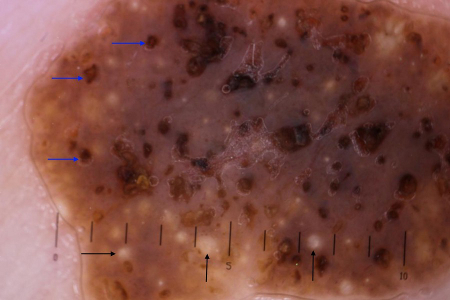

[Figure caption and citation for the preceding image starts]: Typical dermoscopic appearance of seborrhoeic keratosis with milia-like cysts (black arrows) and comedo-like openings (blue arrows)Primary Care Dermatology Society (PCDS); used with permission [Citation ends].

Machine-learning algorithms are being investigated for the purposes of pigmented skin lesion classification (including diagnosis of seborrhoeic keratoses) and early studies are promising but this modality is not widely used in clinical practice yet.[25] The characteristic dermoscopic features of seborrhoeic keratosis are milia-like cysts and comedo-like openings. Milia-like cysts are white or yellowish round structures that correspond to small intra-epidermal, keratin-filled cysts (horn pearls). They are not exclusively found in seborrhoeic keratosis as they are also seen in congenital nevi and papillomatous dermal nevi, but less frequently.

Comedo-like openings (also known as pseudofollicular openings or crypts) are brownish holes in the surface of seborrhoeic keratosis that correspond histologically to keratin-filled invaginations of the epidermis.[7][26] Further dermoscopic criteria include a gyrated surface (brain-like-appearance) and looped vessels. [Figure caption and citation for the preceding image starts]: Dermoscopic image of seborrhoeic keratosis on the chestFrom the collection of Dr Braun and Dr Kolm, used with permission [Citation ends].